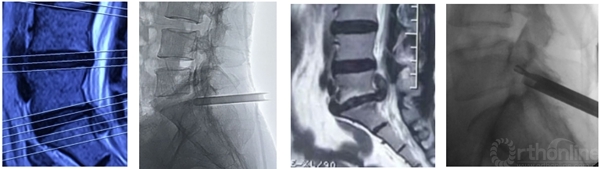

如:入院前通过血液学检查、心电图、胸片等评估基础情况。腰椎正侧位、过伸过屈位,CT/MRI明确是否可以进行脊柱内镜手术。若对诊断可疑,可通过3D-CT、3D-MRI及介入诊断技术等进一步明确。

介入诊断技术:选择性神经根阻滞技术、椎间盘造影技术等,不仅可以从患者的主观感受进一步精准诊断,同时对脊柱内镜手术的疗效可以起到预测作用。

怀疑融合临近节段极外侧突出,选择性神经根阻滞术明确诊断

术前造影显示后纵韧带完整性,术中保护后纵韧带

靶向穿刺